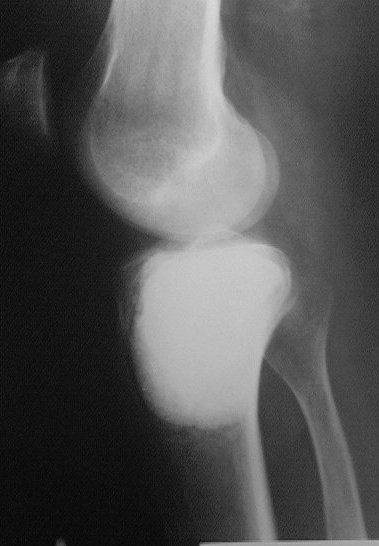

Около года назад больному 25 лет по поводу литической опухоли мыщелка б\б кости ( ОБК?)с выраженным болевым синдромом была произведенарасширенная открытая биопсия, экскохлеация опухоли.

В связи с неясностью диагноза до операции и отсутствия аллокости в тот момент интраоперационно было выполнено экспресс протезирование дефекта мыщелка акриловым цементом. Верхней стенкой дефекта была визуально неповрежденная суставная поверхность. Хрящевая пластина провисала - была выведена на уровень и "подперта" цементным спейсером. Больной осмотрен через год - ходит не хромая, сустав абсолютно спокойный, рентгенологически процедива опухоли нет. Хотелось бы услышать предложения по пластике дефекта - сроки, вид материала. Честно говорябоюсь трогать хрящ повторно.

Случай очень интересный! Увидеть бы снимки до операции. Можно обсудить состояние хряща "на цементе"-за счет чего он жив или там все-таки дефект? Щель сустава хорошая. Есть ли возможность проведения МРТ у больного?